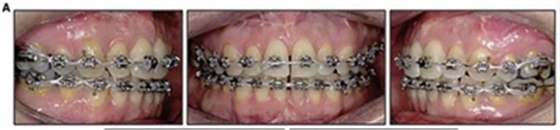

擴弓保持8周后,除擴弓器影響牙外粘接托槽,使用0.014鎳鈦絲進行排齊、整平。旋轉(zhuǎn)停止后3個月拆除擴弓器,全口粘接托槽,使用0.016niti繼續(xù)排齊整平。佩戴可摘保持器,保持上頜寬度。在使用至0.018x0.018niti7周,徹底排齊整平后,使用大弓型的0.016x0.022不銹鋼絲,繼續(xù)維持原有寬度,同時停止使用可摘保持器。掛II類牽,糾正磨牙關(guān)系,使用鏈圈關(guān)閉散在間隙,少量使用IPR去除局部前牙的黑三角。術(shù)后9個月拍全景示,牙根平行度可,再無其他牙根出現(xiàn)問題。1年7個月后治療結(jié)束。上下頜3-3舌側(cè)保持器+哈雷氏保持器進行保持。

患者側(cè)貌改善,下唇唇肌緊張消失,上下唇可自然閉合。磨牙及尖牙關(guān)系糾正至I類,覆合覆蓋正常。上下頜弓型糾正至卵圓形,牙弓寬度增加。頭影測量分析示SNA角81.8°,ANB角3°。頭影測量重疊圖示下頜骨向后旋轉(zhuǎn),垂直面高度略有增加。